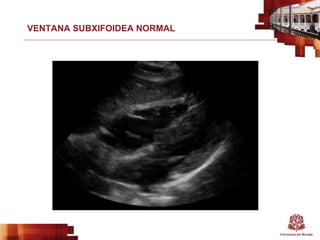

VENTANA SUBXIFOIDEA NORMAL